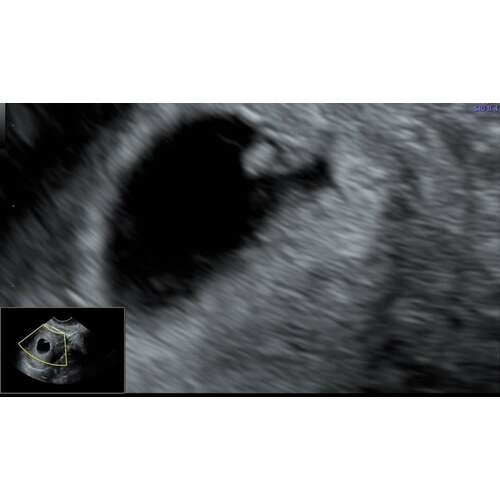

Ik had vandaag ook een goede echo met 6 wk!! Super opgelucht voor nu 😊